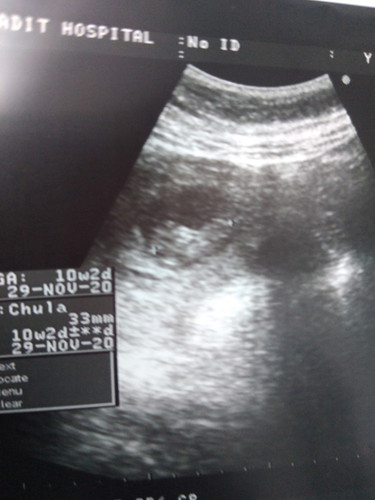

10วีค2วันค่ะ

10วีค2วันคะ

10 w. 2 วันคะ

10w2dค่ะแม่

GA 10w2d ค่ะ

10วิค2วัน

10w2dค่ะ

10w2d จ้า

10w2d ค่ะ